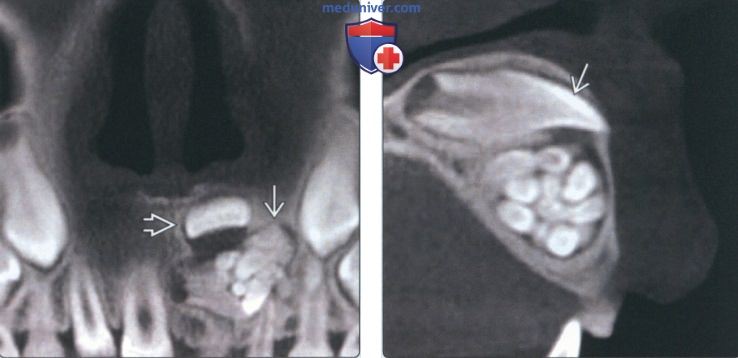

Одонтома нижней челюсти: фотографии и медицинская информация